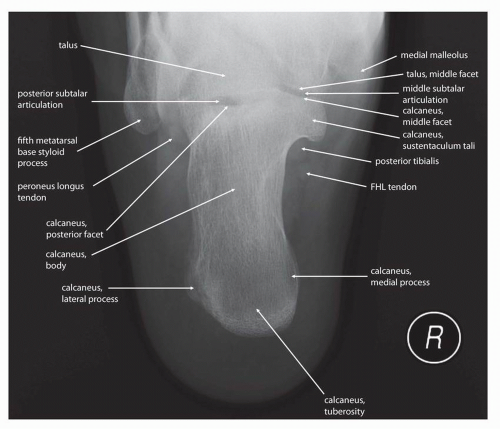

Label the 3 surfaces of the talus that articulate with the calcaneus